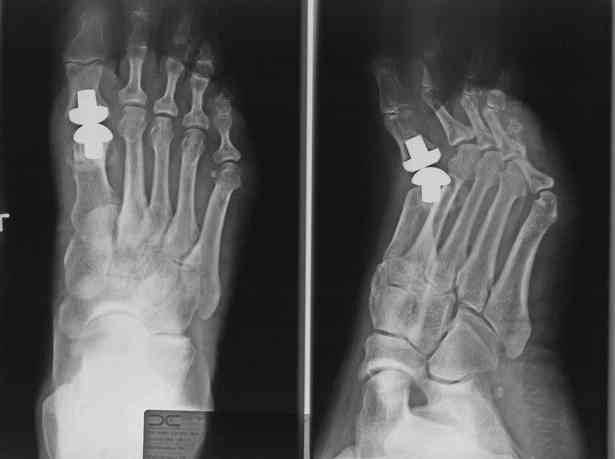

Эндопротез 1 пальца

Уважаемые коллеги,Женщина 55 лет, живет в Литве, жалуется на сильные боли, отечность. Со слов больной по телефону, около года назад, предположительно по повду halluxvalgus, было проведено эндопротезирование плюснефалангового сустава.

Можно предположить нестабильность одного или обейх компонентов эндопротеза (?) Что посоветовать, куда направить на очную консультацию, лечение?